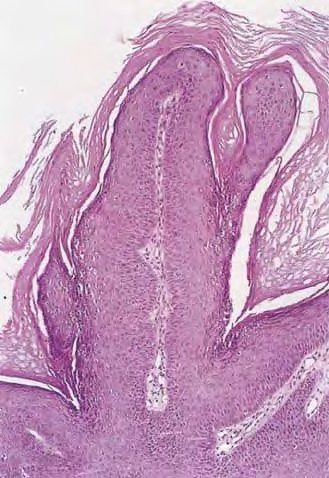

Verruca vulgaris = الثؤلول الشائع